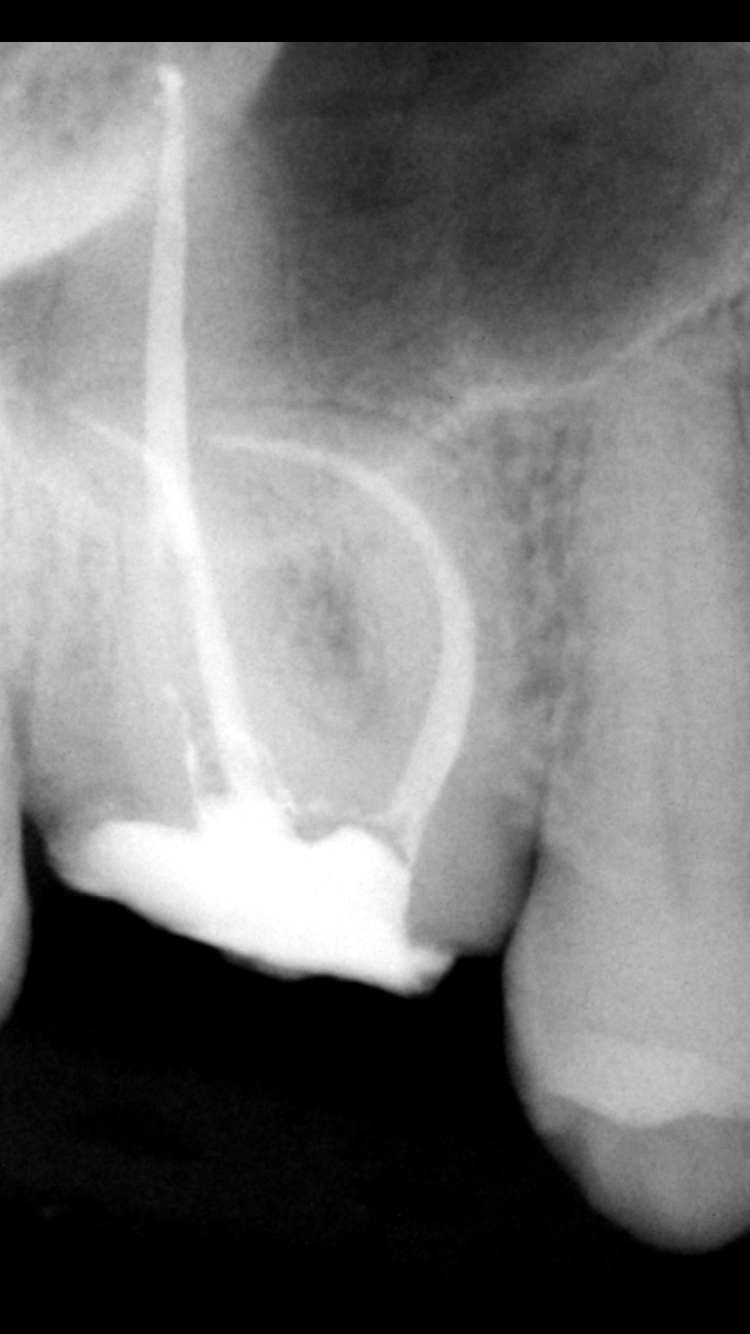

This is a right maxillary first molar (tooth #3) that required root canal therapy because decay developed under an old existing crown. This root canal was complicated because of a severe curvature (dilaceration) in multiple canals. Extra care, time, and the use of additional instruments was required to treat this tooth adequately to avoid future symptoms and infection.